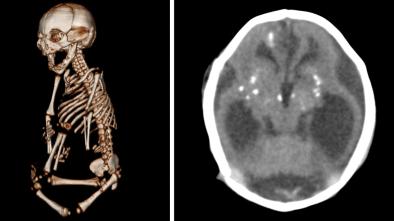

Aug 25, 2016 | NPR

Zika Images Show 'Worst Brain Infections That Doctors Will Ever See'